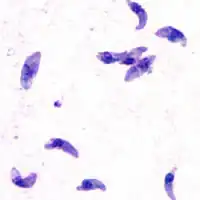

Le parasite Toxoplasma gondii.